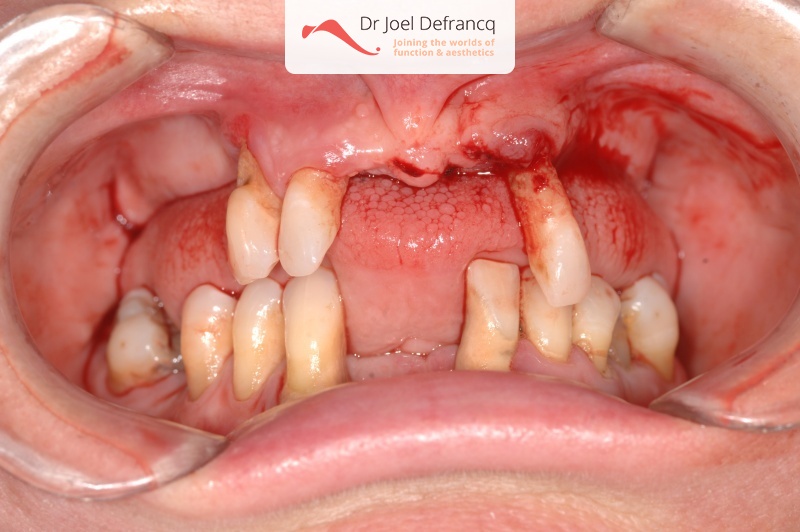

Dentale diagnose

- Klasse I

Behandeling tandheelkundige implantaten

- Vaste tanden op implantaten (bovenkaak)

- Vaste tanden op implantaten (onderkaak)

- Zygoma implantaten